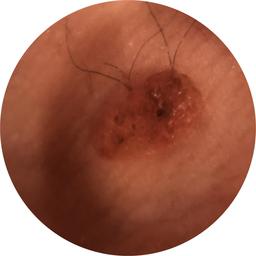

ISIC_4902807

710 x 710

Clinical

Field Value

acquisition_day 207

age_approx 45

anatom_site_1 Upper extremity

anatom_site_general upper extremity

diagnosis_1 Benign

diagnosis_confirm_type single image expert consensus

fitzpatrick_skin_type I

image_type dermoscopic

personal_hx_mm True

sex female